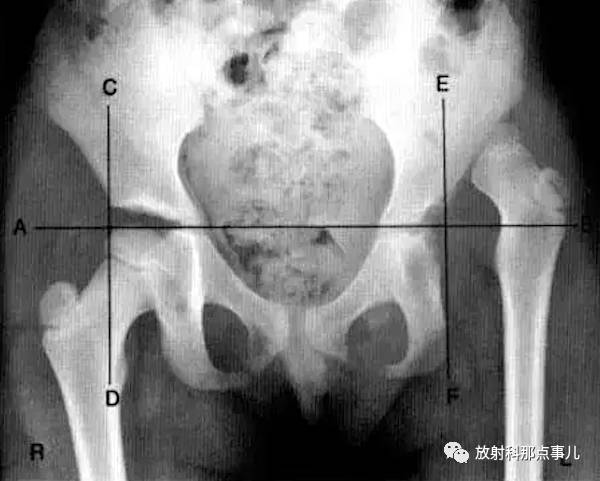

Perkin方格

骨盆正位片,经过双侧髋臼Y形软骨中心划水平线AB,在通过两侧髋臼外商缘引垂线CD和EF,AB线与CD、EF线分别相交,两侧髋关节各分为四个区域称为Perkin方格。正常时,股骨头骨骺中心位于內下区域内,当髋关节发育性脱位时,股骨头骨骺则位于外上区域。